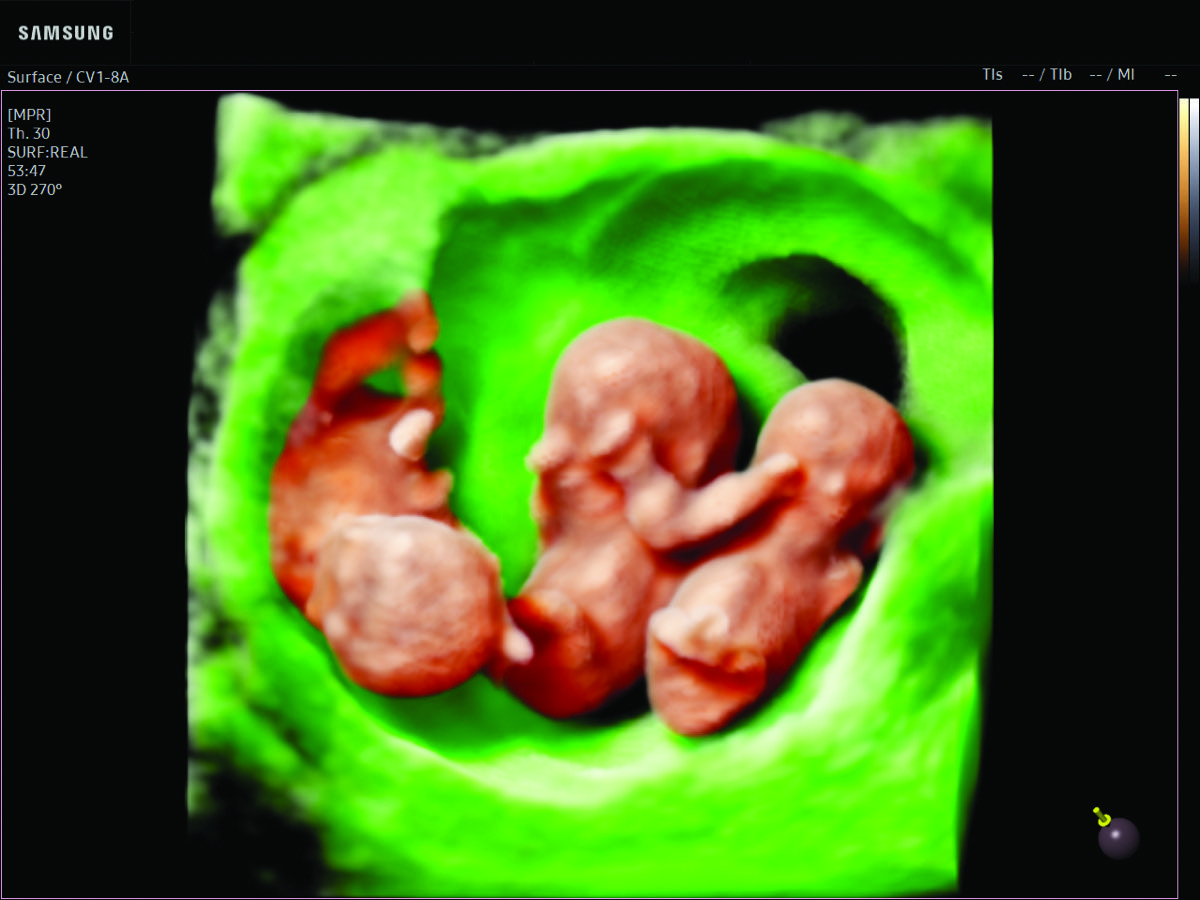

Comprehensive, advanced and expert MFM care for high-risk pregnancies

- Multiple births

- Fetal anomalies